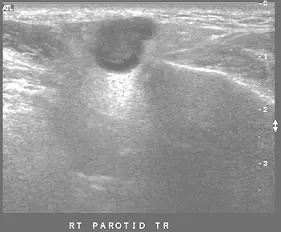

65歲男性病人主訴右臉耳下部位無痛硬塊約 2 年,耳下腺超音波檢查如圖,最可能的診斷為何?

本題提供兩張右耳下腺超音波(RT PAROTID TR)影像:

圖一(B mode / 灰階超音波):

- 耳下腺內可見一個邊界清楚(well-defined)的低回音(hypoechoic)腫塊,形態呈橢圓形至分葉狀(lobulated)。

- 腫塊邊緣清晰,有明顯的包膜(capsule)外觀,與周圍腺體組織有清楚的界限。

- 腫塊內部回音相對均勻(homogeneous),後方回音增強(posterior acoustic enhancement)可見,顯示腫塊實質性但聲學特性偏低阻抗。

- 未見明顯鈣化、壞死或液化區域。